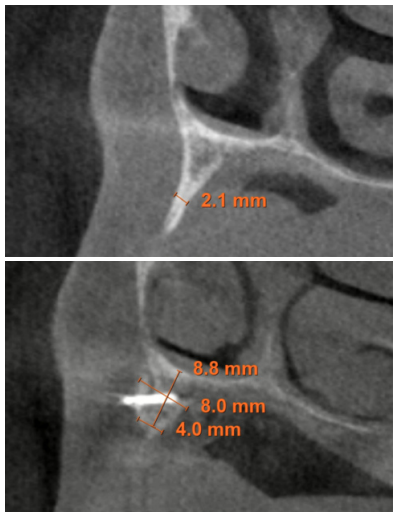

Posteriormente, se procede a la realización de un Cone-beam dental que ofrece una visión más exacta del tipo de rehabilitación implantológica que se pueda plantear. En los cortes correspondientes al maxilar superior, se observan zonas donde puede realizarse la inserción directa de los implantes como las correspondientes a 16 y la zona del incisivo central de este cuadrante (Figuras 4-5) o en el segundo cuadrante el área de 27. En cambio, en la zona correspondiente a los dientes 21 y 23 existe una atrofia horizontal importante, con una anchura ósea residual de aproximadamente 3,5 mm en la zona media de la cresta, con una ampliación en el área más basal de la misma y conservación de ambas corticales. Esto hace que se opte por una técnica de Split de cresta, en este caso en dos fases para poder lograr una mayor anchura final y corregir la inclinación del implante final todo lo posible para lograr una estética en la prótesis final adecuada (Figura 6).

suficiente volumen óseo en anchura y altura para la inserción directa de un implante en esta posición.

En las zonas correspondientes a los dientes 11 y 13 la atrofia horizontal es todavía más marcada. No existe hueso trabecular separando las dos corticales (vestibular y palatina) y la anchura es menor a 2 mm en algunas zonas lo que hace que en esta área se planifiquen injertos en bloque. En la mandíbula se planifican implantes cortos mediante inserción directa, y la zona correspondiente a la rama mandibular será el área donante para los injertos en bloque.